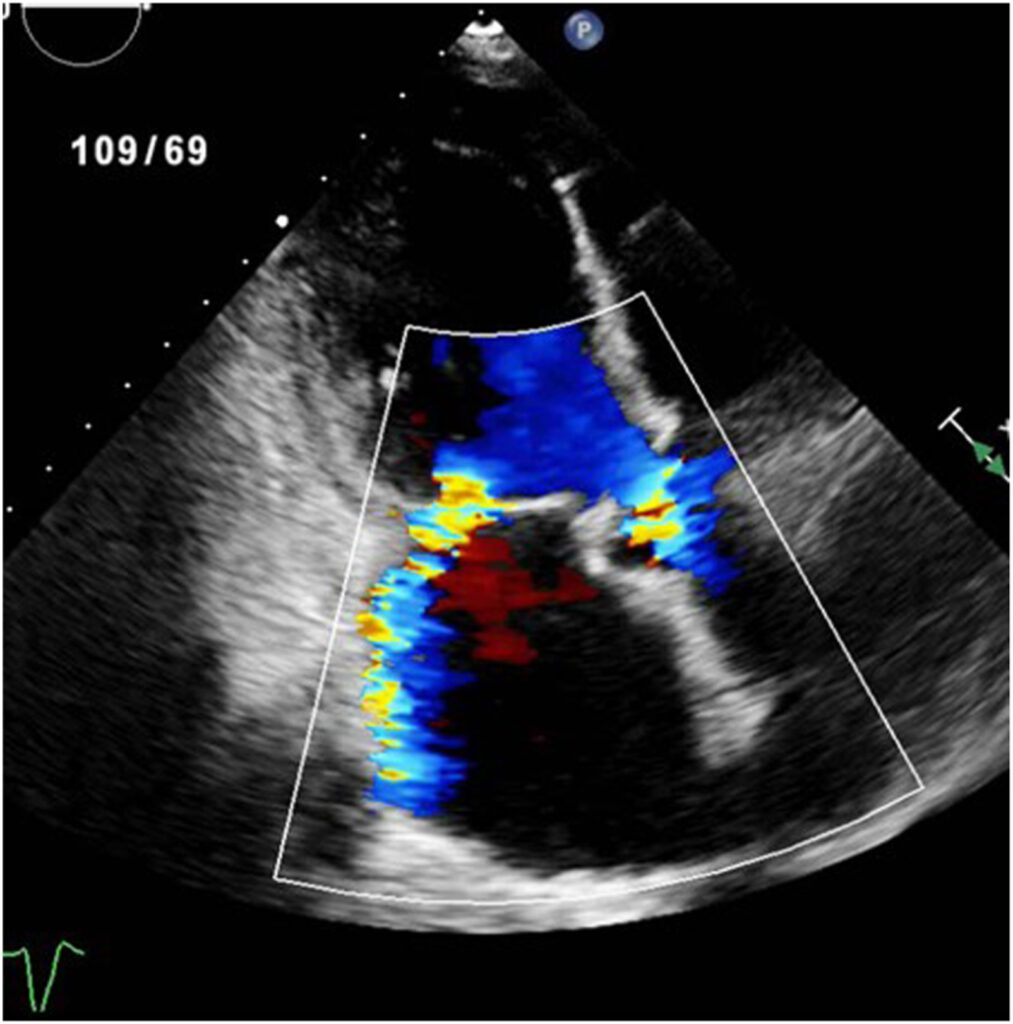

Estudo transesofágico mostrou uma VMi trivalvular com 02 jatos regurgitantes com origem em um folheto posterior dividido.

Akhtar et al, CASE: Cardiovascular Imaging Case Reports, November 2025

Foram observados 03 músculos papilares, embora nenhuma cordoalha relacionada ao cleft tenha sido visualizada.

Dado o alto risco cirúrgico, o paciente foi submetido a reparo valvar borda-a-borda.